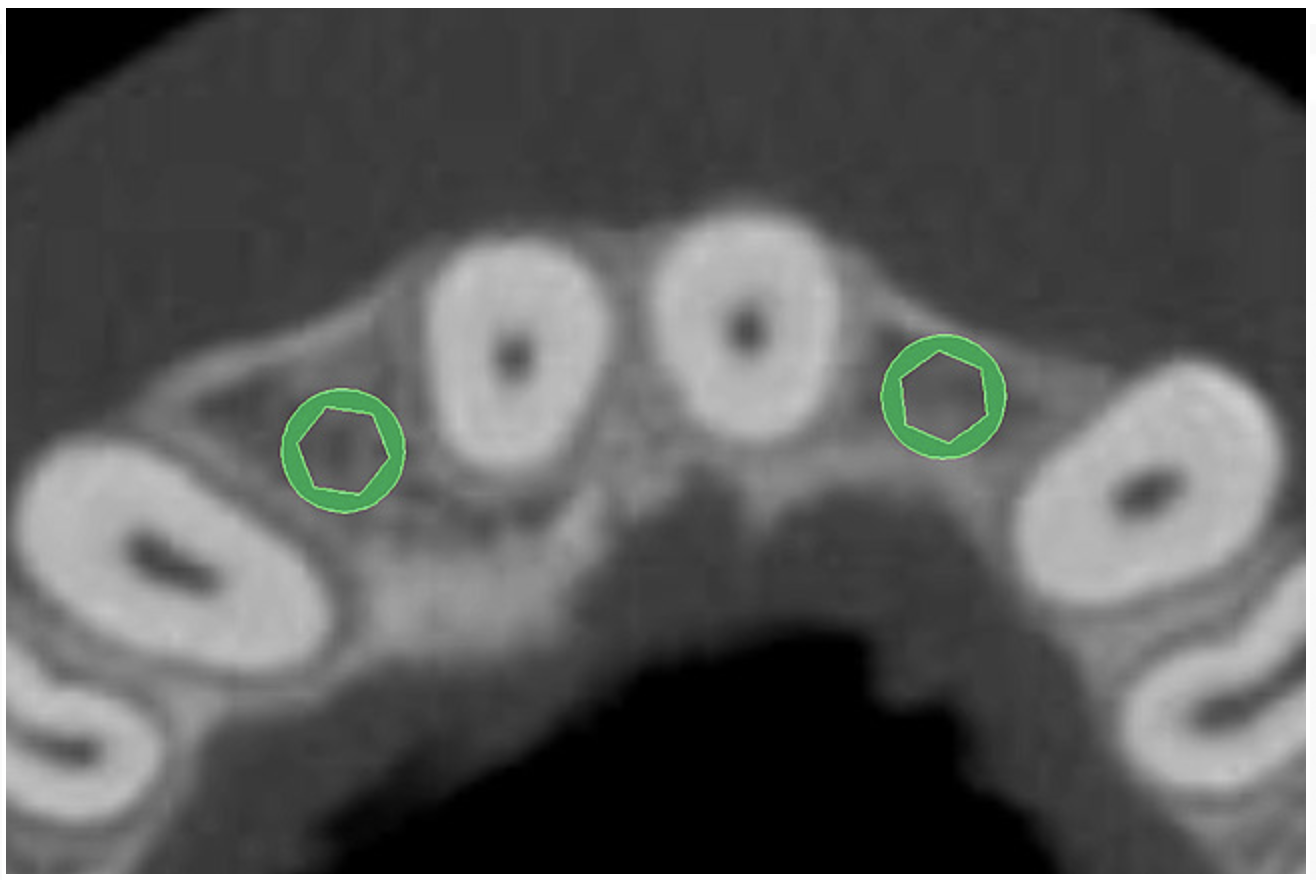

The CT axial views represent an important instrument in gaining a better understanding of anatomical features that can not be determined by any other imaging modality (Figure 6A). When the maxilla is sliced axially at the level where the roots meet the crest of the bone, the adjacent and surrounding root morphology can be revealed. Of note are the individual and different shapes of each of the central incisors, canines, premolars, and molar roots. These images reflect a phenomenon defined by the author as the “restorative dilemma.” Clinicians encounter this often difficult dilemma when attempting to re-establish morphologically correct emergence profiles in prosthetic teeth as they ascend from the round shape of the implant(s). When planning for the placement of the implant in the left lateral incisor area, there appeared to be adequate mesial-distal space between roots as seen in the axial view of Figure 6B. A closer inspection of the planned site for the right lateral incisor revealed a more narrow space, further.complicated by the distal rotation of the palatal aspect of the tooth root. Based on this preliminary position, the 3.75-mm diameter, straight-walled implant can be seen encroaching on the lamina dura periodontal ligament space of the right canine and central incisor. If there was not adequate room for this diameter and type of implant, the adjacent teeth could sustain potential iatrogenic damage. Therefore, additional “tweaking” of the virtual placement was necessary to diminish this risk.

Figure 6a  By slicing the maxilla axially, the images revealed (A) the differing morphology of the central incisors, canines, premolar, and molar roots, and (B) the left simulated implant seen encroaching on the adjacent lamina dura.

Figure 6a

Figure 6b  By slicing the maxilla axially, the images revealed (A) the differing morphology of the central incisors, canines, premolar, and molar roots, and (B) the left simulated implant seen encroaching on the adjacent lamina dura.

Figure 6b